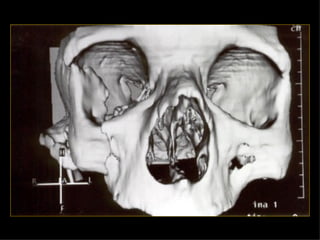

I. Pasa a través de la porción media del maxilar superior II. Piramidal, cruza al etmoides oblicuamente. III. Supracigomatica, comienza en la zona nasal con extension al etmoides.

10% NORMAL Valoraciónclínica No hay deformidad palpable Domicilio Deformidad palpable o herida penetrante Cráneo simple TAC, si la fx cruza ramas de la meníngea media Sospecha Fx base Estudio simple proyecciones para base TAC Examen neurológico anormal Sospecha de lesión 60% Agresiones 17% Acc. Autom Otras

I. Pasa através de la porción media del maxilar superior II. Piramidal, cruza al etmoides oblicuamente. III. Supracigomatica, comienza en la zona nasal con extension al etmoides.